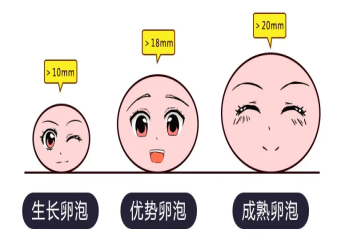

超声下卵泡监测

超声下卵泡监测是最准确了解卵泡发育情况、排卵情况、排卵时间的监测方法,经济且无创,同时还可以了解哪一侧卵泡排卵,根据卵泡形态初步判断卵泡的大小及质量,唯一缺点是这一步需要到医院监测。